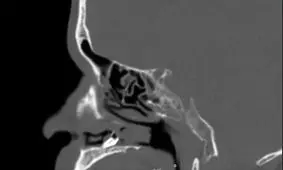

مردی که به دلیل انسداد مجرای بینی، قابلیت بویایی خود را از دست داده بود، با مراجعه به پزشک متوجه شد، دندانی درون بینی او روییده است.